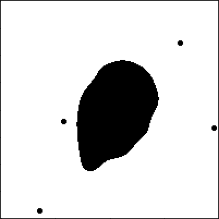

3 Simulation Study

We conduct simulation studies under two scenarios. For each scenario, we randomly generate 100 binary tumor images of size pixels from two groups of A and B, respectively, and create 30 independent datasets. In scenario 1, the main tumor region is created by applying Gaussian smoothing and thresholding to 50 points sampled from the bivariate normal distribution. Then, up to 5 and 20 random points are added as small tumor regions to groups A and B, respectively. The two groups mainly differ by the number of small disconnected tumor regions, summarized in quadrant IV of the dimension-zero persistence diagram, as illustrated in Figure 2(a). In scenario 2, larger main tumor regions are created similar to scenario 1, and up to 20 small tumor regions are added to both groups. For group B, up to 50 holes are created around the boundary of the main tumor region. The tumor region with holes corresponds to topological features in quadrant III of the dimension-zero persistence diagram, as shown in Figure 2(a). The simulated tumor image examples of two groups are given in the left panels in Figures 4(a) and 4(b).

We transform the simulated images by the SEDT for two-class (SEDT-2). The SEDT-2 is a simpler version of the SEDT-3; it does not assign infinite values because the generated images do not have empty regions. Interpretation of the topological shape features of binary images is similar to interpretation of the three-class images shown in Figure 2, except that there are no topological features that summarize separate non-tumor regions (e.g., E and F in Figure 2(a)).

Persistent homology is computed as illustrated in Section 2, and the results are represented as persistence surface functions using smoothing parameters . We replace the dimension-zero persistence result with infinite death value with .

The functional coefficients of the proposed model show which shape patterns contribute the most to hazard. The average estimated dimension-zero functional coefficients are shown in the right panels in Figures 4(a) and 4(b). The coefficients show how topological features are associated with the survival prognosis; the blue-colored and red-colored areas are positively and negatively related to the hazard function, respectively. Thus, if a larger number of topological features appear in the blue (red) region, it is associated with higher (lower) hazard. For scenario 1, the topological features summarized in quadrant IV of the dimension-zero persistence diagram in Figure 4(a) are positively associated with hazard. This is consistent with group B having a larger number of small disconnected tumors than group A. Also, for scenario 2, the topological features that appear in quadrant III near the origin of the dimension-zero persistence diagram in Figure 4(b) are related to higher hazard. This corresponds to the tumor regions created by small holes. The red-colored region around in Figure 4(b) shows the difference of the size of tumor regions. Because the holes are added to the main tumor region in group B, its size, measured by the radius of the largest circle that can be placed inside, is smaller than that of group A. The coefficient of dimension-one functional predictors is not reported because they are not selected for more than half of the datasets.